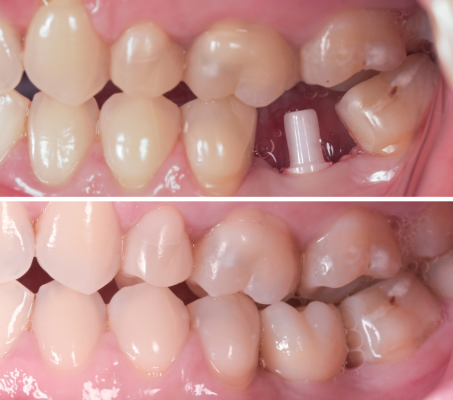

Fotoğrafın solunda titanyum, sağındaysa seramik implant kullanılarak yapılmış dişleri görmektesiniz. Diş etinin yapısı ve rengindeki farkı gözlemlemek mümkün.

Diş eti, zirkonya implantların çevresini doğal olarak sarma eğilimindedir ve titanyum implantlarda gerekebilen diş eti ekleme işlemlerine zirkonya implantlarda genelde gerek olmaz. Seramik implantlar, insan dokularıyla uyumluluk gösteren zirkonyadan yapılmıştır. Hipoalerjeniktir ve metal implantlarla oluşabilecek alerjik reaksiyon ve iltihap riskini önemli ölçüde azaltır.

Titanyum ve seramik implantlar arasındaki belki de en belirgin ama basit fark renktir. Beyaz bir malzeme olarak seramiğin estetik özellikleri, özellikle ince veya hassas yumuşak doku biyotipine sahip hastalarda veya yumuşak doku çekilmesi vakalarında kendini gösterir. Zirkonya implantlar ayrıca titanyuma göre daha az mukozal renk değişikliğine yol açar.